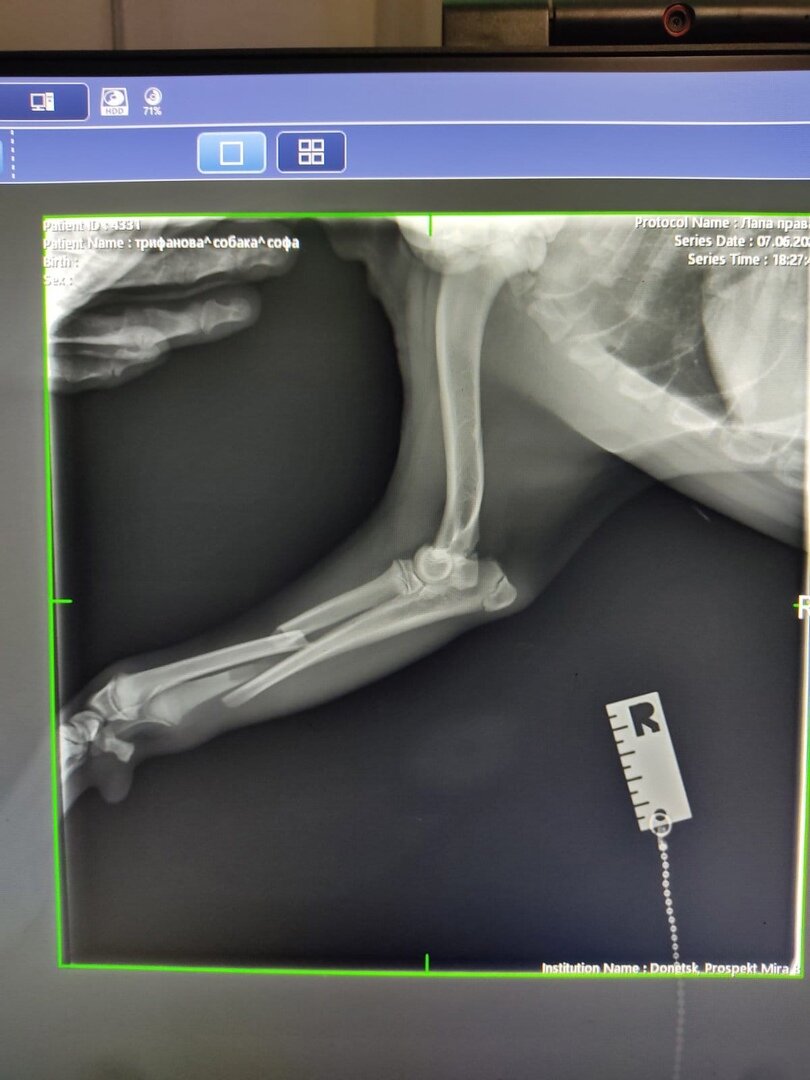

Подростка Софу сбила машина в районе ЖД, сломаны передняя и задняя лапки... Уже прооперирована.

Просим помощи в лечении Софочки! Это бездомный щенок и совсем нет никому дела до неё ….(((